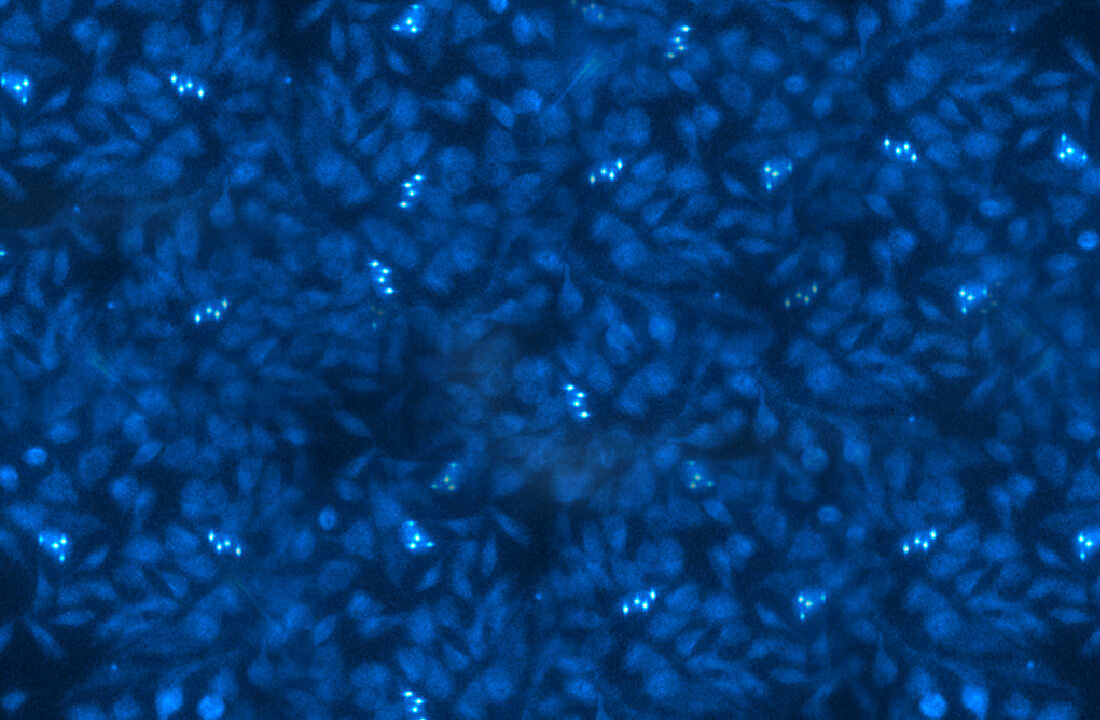

We investigate brain functions and diseases

through optics and aquadynamics.